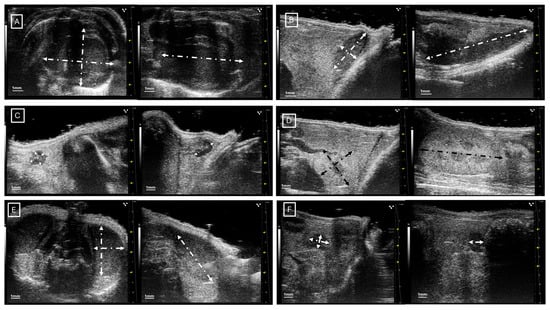

Figure 1 and Figure 2 show examples of ultrasound and microCT diameter measurements. Figure 3 shows examples of manual segmentation.

Figure 1.

Representative images of ultrasound diameter measurements in (A) heart in axial (left) and longitudinal (right) views, (B) spleen in axial (left) and longitudinal (right) views, (C) inguinal lymph nodes in axial (left) and longitudinal (right) views, (D) left kidney in axial (left) and longitudinal (right) views, (E) left testicle in axial (left) and longitudinal (right) views, and (F) left ovary in axial (left) and longitudinal (right) views. In all cases, the diameters are marked with dotted, white, or black lines.